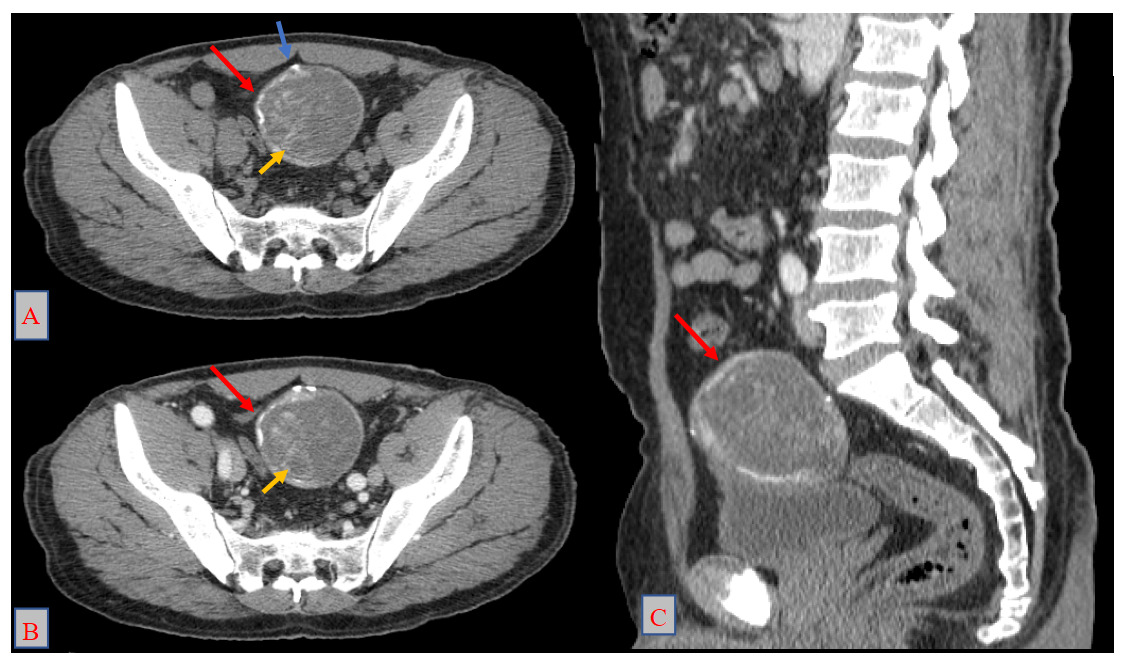

Physical examination was unremarkable. Abdominopelvic ultrasound revealed a supravesical cystic lesion with a thickened wall, classified as Gharbi type III, measuring 53 × 61 mm (Figure 1). Contrast-enhanced CT confirmed a well-defined supravesical cyst, approximately 80 × 60 mm, displacing the bladder inferiorly, with no evidence of adjacent tissue invasion or other hydatid localizations (Figure 2). Serological testing for hydatid disease was positive, further supporting the diagnosis.

_axial_section_before_contrast_injection__(b)_axial_section_after_contr.png)